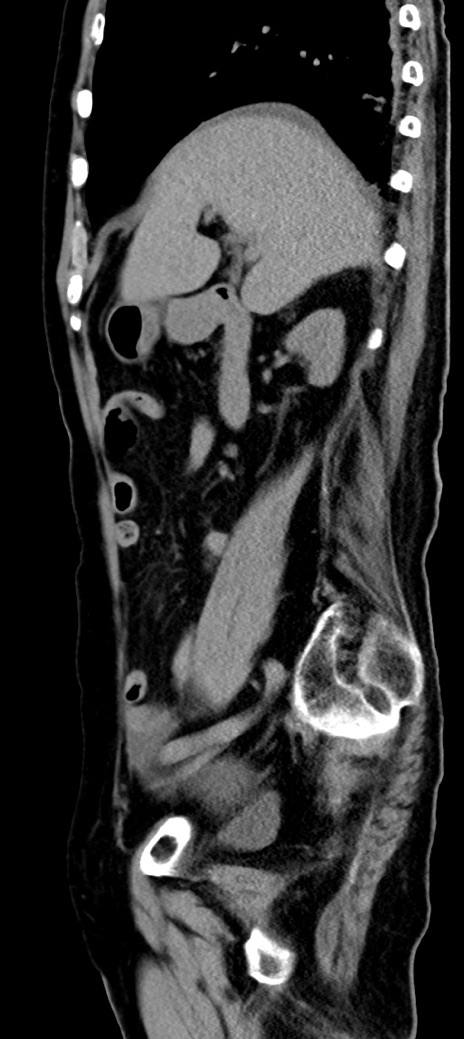

症例40(矢状断像)他院1日前

【症例】90歳代女性

【主訴】腹痛・嘔吐

【現病歴】 食欲低下、嘔吐があり昨日他院受診。肺炎と診断され入院となる。入院後より腹部全体に圧痛あり。胃管留置され経過みていたが、症状持続するため、

当院転院となる。

【既往歴】胸椎圧迫骨折、胆石症

【身体所見】腹部:中央に激痛あり、圧痛あり、反跳痛不明

【データ】WBC 17100、CRP 18.82